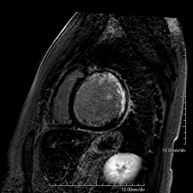

- RM Cardíaca

Es una prueba diagnóstica no invasiva que obtiene información morfológica y funcional del corazón y las estructuras adyacentes; de esta manera se pueden diagnosticar diferentes patologías congénitas y adquiridas, o bien realizar controles en pacientes con patología previa ya conocida. En la gran mayoría de casos es necesario el uso de contraste intravenoso (gadolinio) para completar el estudio, un tipo de contraste que raramente produce reacciones adversas. Durante la prueba, el técnico le pedirá varias veces que aguante la respiración durante 10-15 segundos para obtener las imágenes lo más claras posible. No se necesita preparación previa alguna por parte del paciente. La duración de la prueba es de aproximadamente 45-60 minutos. Está contraindicada en pacientes con marcapasos; el paciente debe avisar si es portador de implantes metálicos y/o clips quirúrgicos.